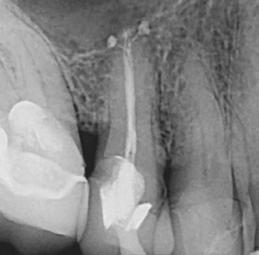

Figure 1: A PA X-ray showing a failed root canal treatment on a lower incisor (left) and the corresponding endodontic microsurgery (right) showing the original oval and missed anatomy of the canal. Courtesy Dr. Bertrand Khayat, Paris, France Dr. Chafic Safi treating a patient at his practice, Centre Endodontique Saint-Laurent, in Montreal, Canada

Traditional endodontic files cannot enlarge the natural cross section of the root in all directions; rather they induce a round shape, leaving large areas untouched and packing debris in the oval extremities.3 This prevents adequate cleaning and disinfection (Figure 1). Moreover, the more a canal is tapered with traditional instruments, the thinner and the weaker the tooth becomes. Traditional rotary instruments have consistently been shown to create dentinal defects and cracks that are suspected to lead to root fractures.4 Even reciprocating techniques create dentinal cracks, without mentioning their debris extrusion into the periapical tissues.5,6